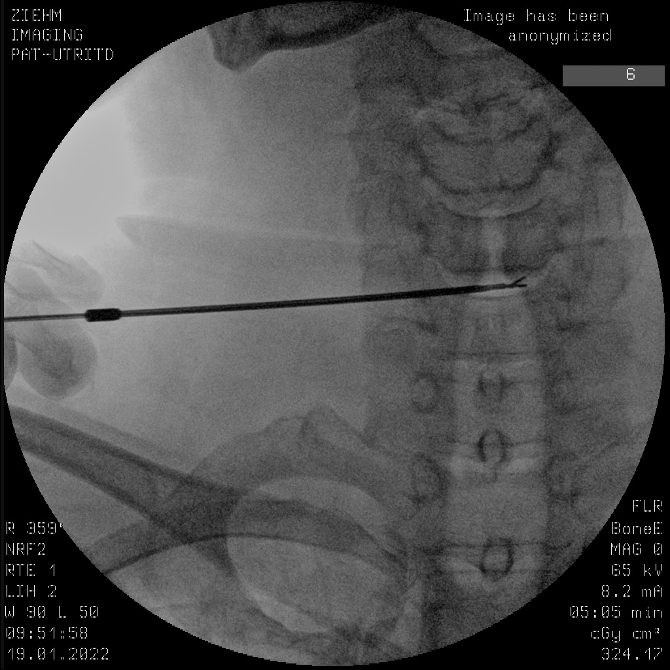

頚椎椎間板ヘルニア、腰椎椎間板ヘルニアに対する治療として外来の神経ブロック以外に経皮的髄核摘出術(DART)を施行しております。保険適応であり1泊2日の入院にて施行可能です。局所麻酔のみで行う超低侵襲手術となっております。詳しい話をご希望の方はお気軽に来院してください。wink